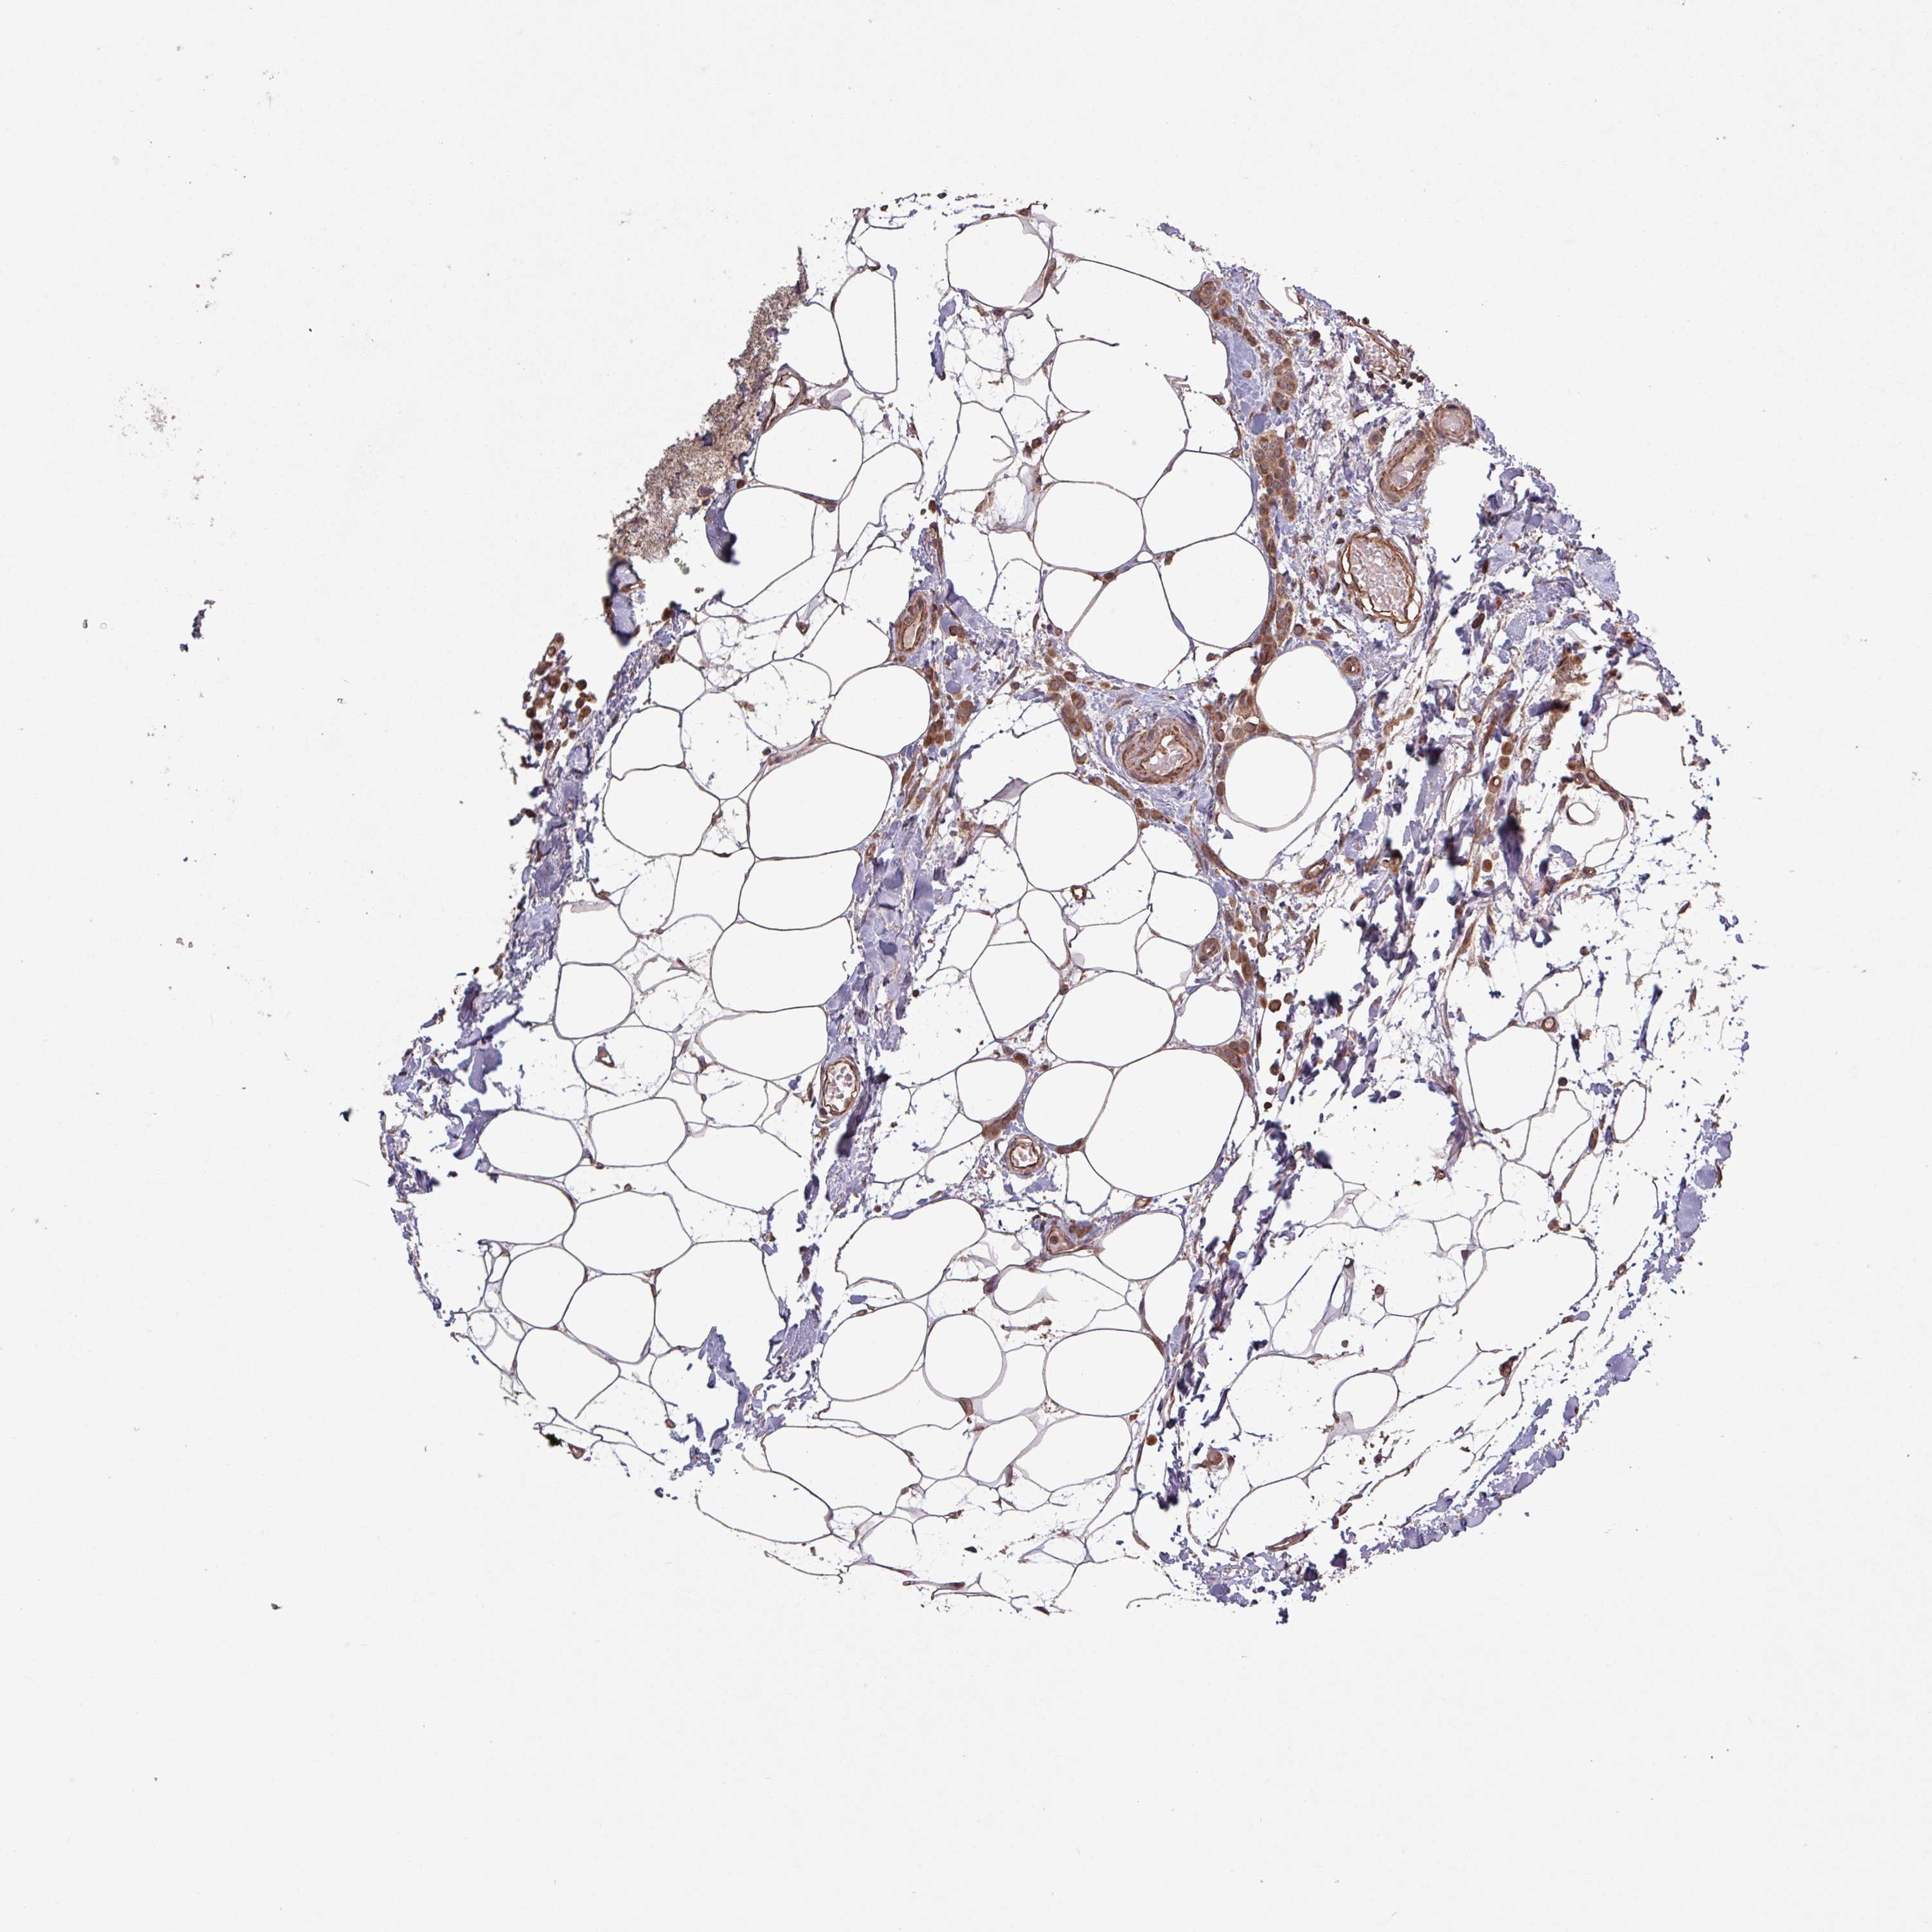

BRCA TCGA BRCA VALIDATION PROTEIN EXPRESSION

ANTIBODIES

AND

VALIDATION